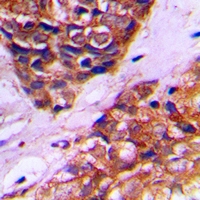

IHC (Immunohiostchemistry)

(Immunohistochemical analysis of PEX10 staining in human prostate cancer formalin fixed paraffin embedded tissue section. The section was pre-treated using heat mediated antigen retrieval with sodium citrate buffer (pH 6.0). The section was then incubated with the antibody at room temperature and detected using an HRP conjugated compact polymer system. DAB was used as the chromogen. The section was then counterstained with haematoxylin and mounted with DPX.)